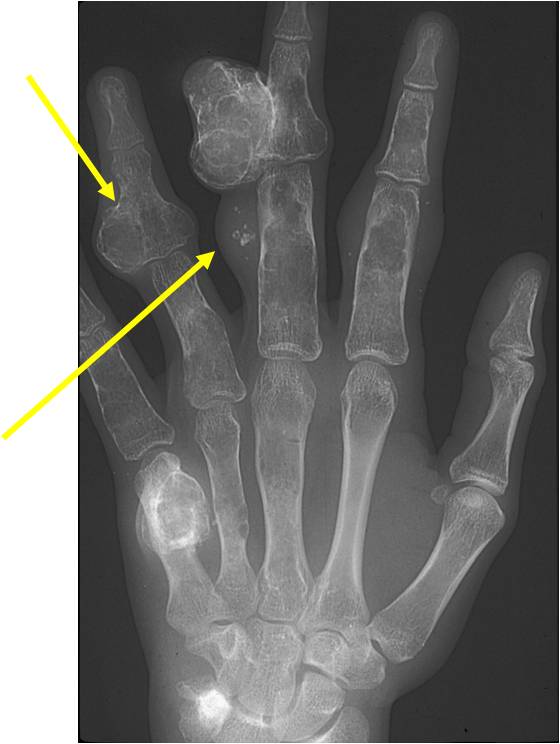

Geographic Lesion Bony Expansion Minimal Calcification Some Enchondromas do not calcify

Geographic lesion Stippled calcifications in lesion Phalanx is expanded Significant endosteal scalloping No cortical destruction No soft tissue extension Cortex Scalloped and Expanded